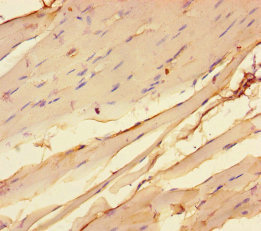

CHRNA1基因位于人類2號(hào)染色體q31.1,編碼煙堿型乙酰膽堿受體(nAChR)的α1亞基。該蛋白含457個(gè)氨基酸,具備四個(gè)跨膜結(jié)構(gòu)域(M1–M4),其中M2形成離子通道孔道,負(fù)責(zé)陽(yáng)離子通透 [1]。在神經(jīng)肌肉接頭(NMJ),CHRNA1與β1、δ、ε/γ亞基組裝為五聚體受體,介導(dǎo)乙酰膽堿(ACh)信號(hào),引發(fā)肌細(xì)胞膜去極化與肌肉收縮 [2][3]。

Human muscle nAChR apo state (圖源:PDB)

基因敲除實(shí)驗(yàn)表明,CHRNA1缺失會(huì)導(dǎo)致NMJ突觸后膜發(fā)育異常并阻斷信號(hào)傳遞,突顯其在突觸形成和功能維持中的關(guān)鍵作用 [2]。此外,CHRNA1胞內(nèi)環(huán)區(qū)可與rapsyn結(jié)合,確保受體在突觸后膜高密度聚集 [4]。其M3-M4連接區(qū)的磷酸化修飾還可調(diào)控受體內(nèi)化速率,對(duì)突觸可塑性具有重要意義 [3]。成人骨骼肌中,ε亞基替代胎兒γ亞基,提高通道電導(dǎo)率,該亞基轉(zhuǎn)換依賴agrin-MuSK信號(hào)通路調(diào)控 [5]。